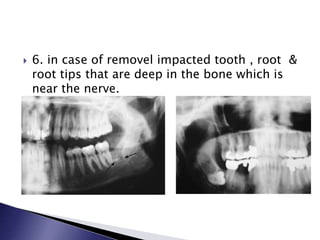

 6. in case of removel impacted tooth , root &

root tips that are deep in the bone which is

near the nerve.

 6. incase of removel impacted tooth , root & root tips that are deep in the bone which is near the nerve.